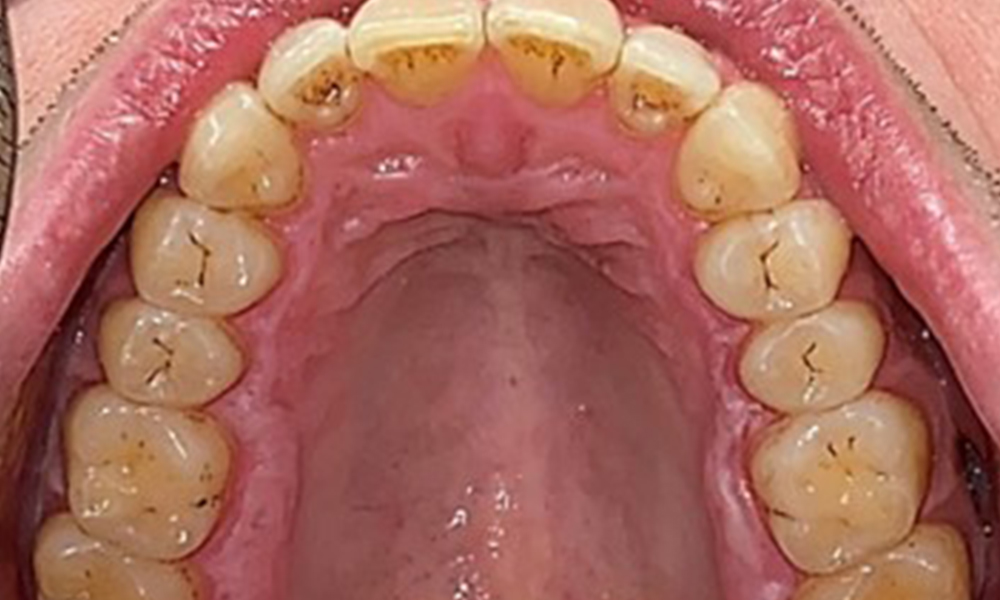

Il n'y a pas eu de résultats pathologiques extra-oraux. Lors de l'examen intrabuccal, l'inspection de la vue frontale a révélé une décoloration brunâtre près de la gencive kératinisée et à la transition vers la muqueuse mobile (Fig. 2), qui pourrait être attribuée à la consommation de nicotine. Des lésions blanchâtres de la muqueuse ont été observées sur le palais, en particulier près des surfaces palatines des molaires maxillaires, ce qui indique une kératinisation accrue et peut également être attribué à la consommation de nicotine. La langue était recouverte d'un enduit amovible blanc et brunâtre.

Le patient a une dentition complète avec un total de 28 dents. Il y avait des érosions et des attritions notables. (Fig. 4, Fig. 5). En raison du bruxisme, le patient a porté pendant de nombreuses années une attelle avec une gouttière ajustée la nuit. Les érosions ont été causées par une consommation prolongée de boissons isotoniques. Aucune perte d'os parodontal ou carie active n'a été observée.

Une denture adulte complète, sans carie ni perte osseuse radiologiquement reconnaissable, a été observée (Fig. 6). La perte radiologique d'émail et de cuspides était particulièrement évidente sur les 36 et 37.